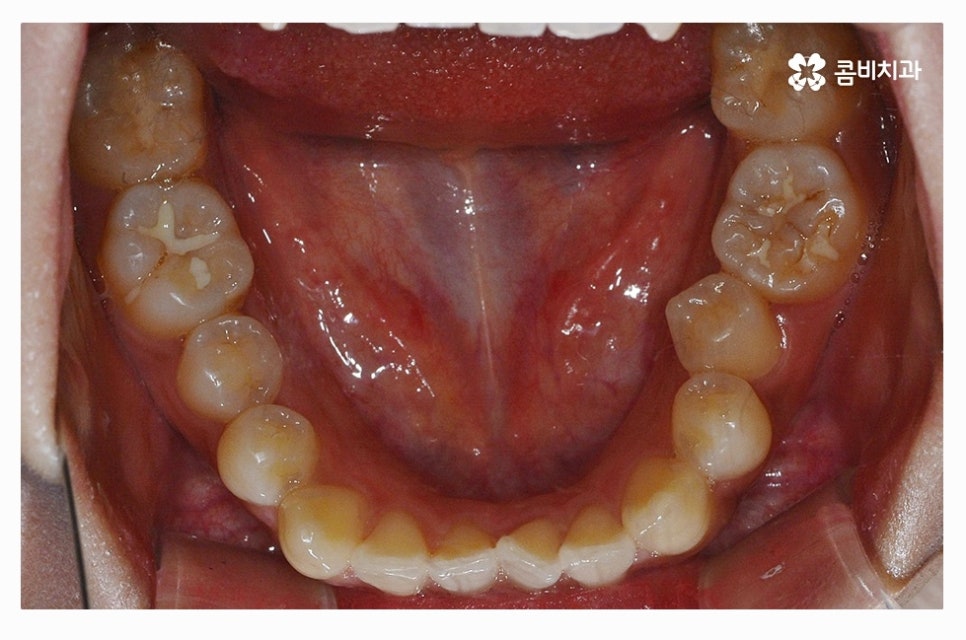

출처 아카이브 열기덧니의 이유는 다양하지만 일반적으로는 유치를 늦게 발치하거나

턱뼈가 좁은 경우, 치아 크기가 큰 경우, 습관

유전적 요인과 환경적인 요인으로 나눌 수 있는데요.

덧니를 방치하게 되면 구강관리의 어려움으로 잇몸이나 충치질환이

발생할 가능성이 상대적으로 높고, 치아의 기능적인 부분과

심미적인 부분을 고려했을 때 덧니교정을 하는 것이 필요할 수 있어요.

덧니는 치아 사이에 음식물이 끼기 쉽고 치석이 쌓여서

충치 및 잇몸질환이 발생할 수 있으며 덧니로 인한 부정교합이나

턱관절 장애가 발생하는 경우도 있기 때문에 덧니의 정도에

따라서 꼭 덧니교정을 하는 것이 이로운 분들이 있는데요.

덧니의 형태는 개개인에 따라 다르지만 덧니로 인해

치석이나 음식물이 방치되기 쉽기 때문에 나이가 들수록

충치 및 잇몸병에 시달리게 되는 확률이 높아질 수 있어요.